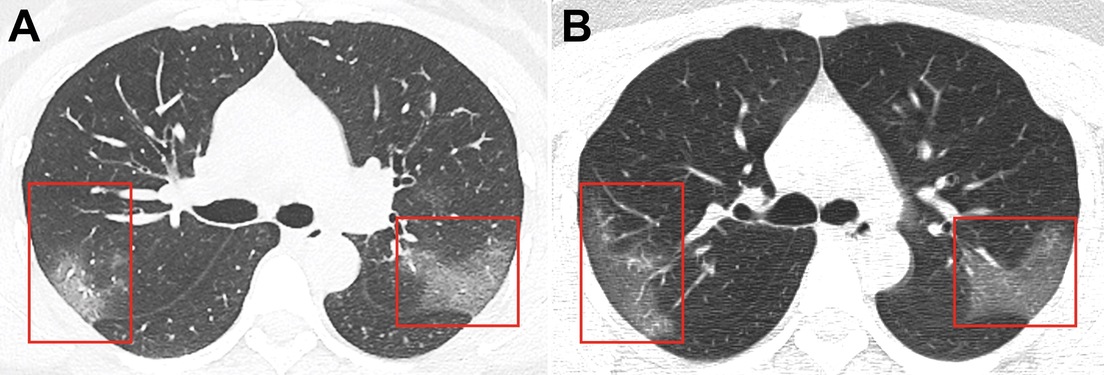

A través de las radiografías, los médicos observaron unas manchas blancas en la esquina inferior de sus pulmones, llamadas por los especialistas como la "opacidad de vidrio esmerilado".

Pero en este caso, los investigadores detectaron que las manchas se extendían hasta los bordes de los pulmones de la mujer, una característica que también se había detectado en los pacientes con SARS y MERS. Lakhani indicó que en las imágenes detectaron que el nuevo brote tiene "muchas características similares" con las otras dos epidemias.

Para descartar que no se tratara de una neumonía, los especialistas repitieron las radiografías al cabo de 3 días, cuando la paciente ya había recibido su tratamiento, y descubrieron que las manchas blancas se habían vuelto más extensas y pronunciadas.